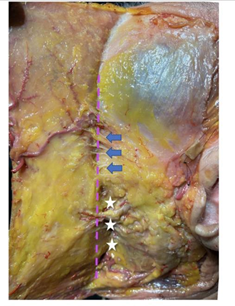

Figure 5 Cadavérica dissection of the left side of the face exposing the SMAS, superficial temporal fascia with the superficial temporal artery and the temporal fascia (upper face), and the parotid masseteric fascia (middle and low face). The blue arrows mark the masseteric ligaments on the anterior border of the masseter muscle (posteriorly to the mandibular ligament). The dashed pink line represents the functional ligament line (fLL).7 (Autorized by Eliandre Palermo, MD and Andre Braz, MD).